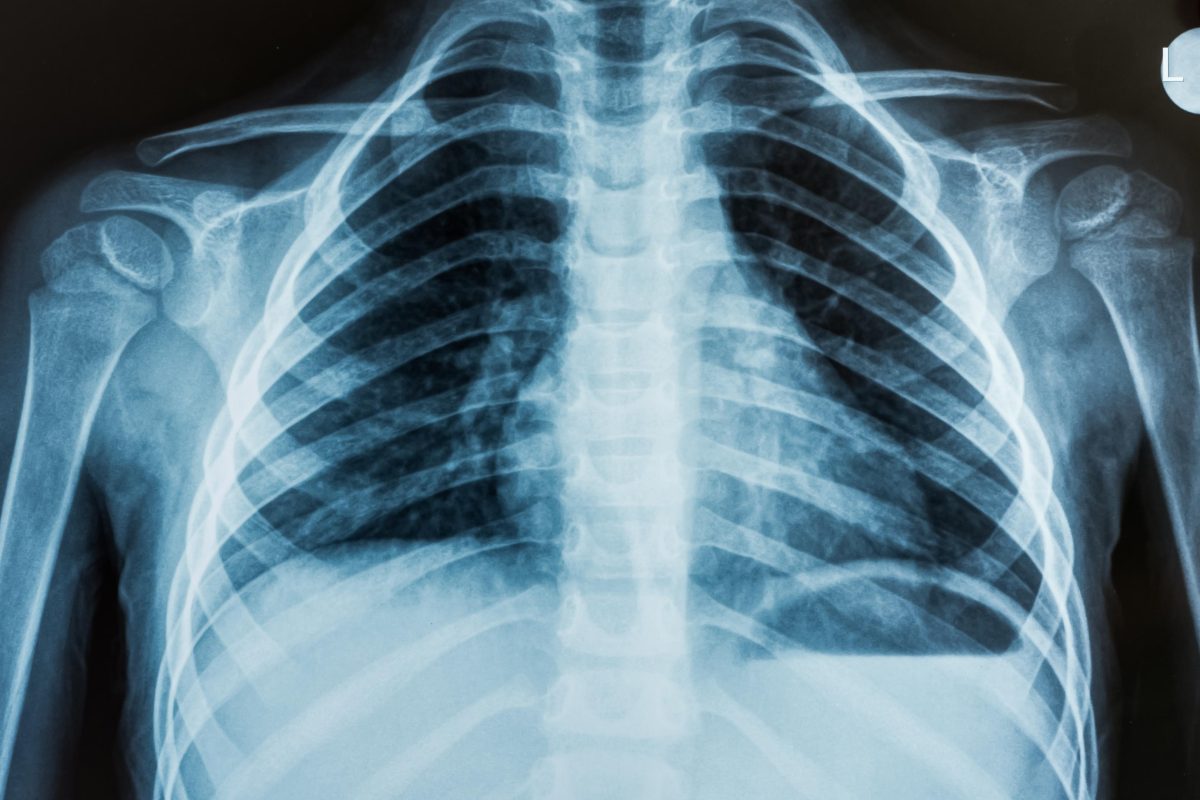

Xray

This department offers radiological investigations to in patients and out patients from the hospital,

other public and private health institutions. The department is able to perform ultrasounds and x-rays.

The hospital hopes to expand the infrastructure to accommodate a CT-Scanner and mammogram.